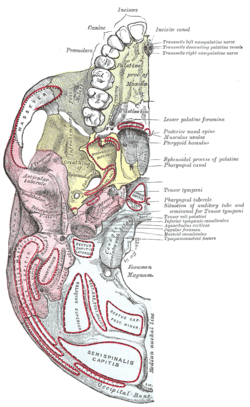

Base of the skull. Upper surface Base of the skull. Inferior surface, attachment of muscles marked in red

Base of the skull. Inferior surface, attachment of muscles marked in red